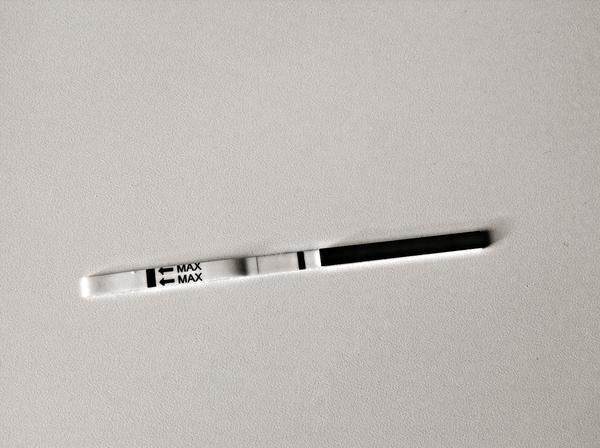

@zuzannaaa tu to skôr vyzera ako kanálik...no dufam že ciarku mas aspoň troska ruzovu

@veronika1603 dakujem ti, si zlata,ale dnes 1 dc ☹ ☹ ☹ ..ta ciarka mala aj hrubku a aj ruzovu farbu...a nic...som smutna...sklamana a nastvana!!!...verim, ze o mesiac sa budeme tesit z dvoch ciarok a budu to carovne vianoce 🙂

Baby myslite ze mam este sancu ked mi 3 dni meska teraz som si robila test vyzeral negativny ale aj ta negativna palicka bola taka nevyrazna a hlavne miestami prerusovama, zajtra skusim znova.